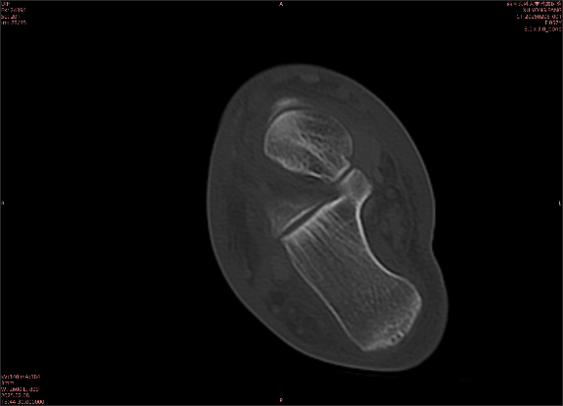

舉例圖像

圖2

專業(yè)解釋看不懂沒關(guān)系,大家看圖1和圖2就可以了,這是同一個患者跟骨的磁共振和CT圖像,圖1的紅色箭頭指示的黑線就是磁共振圖像顯示的骨折線,一目了然。而對比圖2的CT圖像上并未顯示異常。

這下大家明白了吧,如果懷疑隱匿性骨折優(yōu)先選擇磁共振檢查